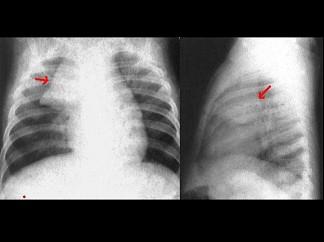

男性,10岁。胸闷、气短,呼吸困难。X线检查如图,最可能的诊断为?(?)A.心包炎B.心包积液C.先天性ASDD.先天性VSDE.心肌炎

问题 男性,10岁。胸闷、气短,呼吸困难。X线检查如图,最可能的诊断为?(?)

选项 A.心包炎 B.心包积液 C.先天性ASD D.先天性VSD E.心肌炎

答案 B